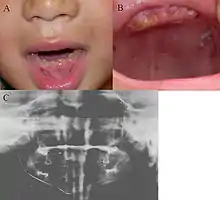

| Oral photographs from an individual with Dentinogenesis imperfecta | |

This condition can cause teeth to be discolored (most often a blue-gray or yellow-brown color) and translucent, giving teeth an opalescent sheen.[2][3][8][5][9] Teeth are also weaker than normal, making them prone to rapid wear, breakage, and loss.[2][3][4][5][8] These problems can affect baby (primary/deciduous) teeth alone, or both baby teeth and adult (permanent) teeth, with the baby teeth usually more severely affected.[5][8]

Clinical features include:

- Discoloured teeth - teeth may be amber, brown, blue or opalescent

- Bulbous shape to the tooth crown due to cervical constriction

- Tooth wear/Non-carious tooth surface loss (NCTSL) - due to the poorly mineralised dentine, the enamel of the tooth is unsupported and subsequently shears or chips off as it is subjected to biting forces. This exposes the underlying poorly mineralised dentine which is less resistant to wear. Therefore, features of abrasion and attrition may become apparent.

- Reduction in occlusal vertical dimension (OVD) - this is secondary to the tooth wear/NCTSL. A reduced OVD can lead to craniofacial dysgnathia, poor tooth aesthetics, and disorders during chewing, swallowing, speaking and eating.[2][3][4][5][8]

The baby (primary) teeth are usually more severely affected than adult (permanent) teeth.[3][5][8]